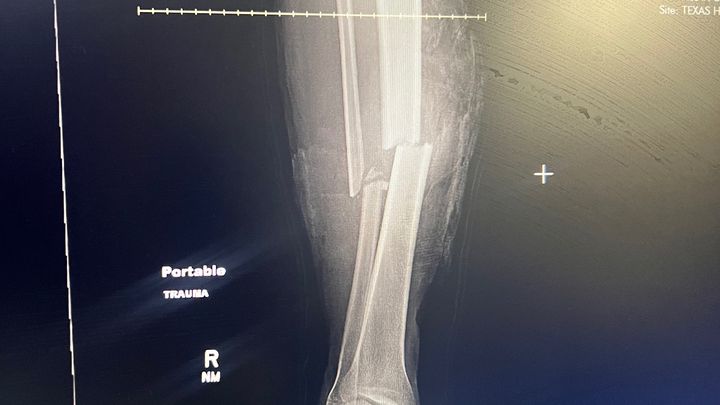

I AM HOME NOW, I GOT 6 WEEKS UNTIL I CAN WALK AGAIN. I HAD ONE OF THE BEST SURGEONS IN DFW. MY SURGERY WENT FROM 6MONTH PROCESS TO 6WEEKS. CANT WAIT TO GO BACK TO WORK.